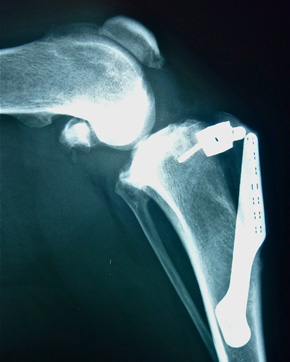

• Knochen- und Gelenkschirurgie (Beinbrüche, Kreuzbandriss (Bandersatz und TTA), ED, OCD, Patellaluxation)